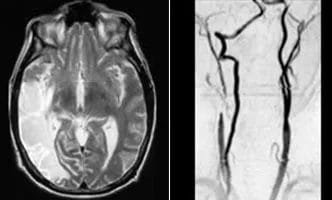

Carotid-Dissection-cover

Carotid Dissection and Recanalistation